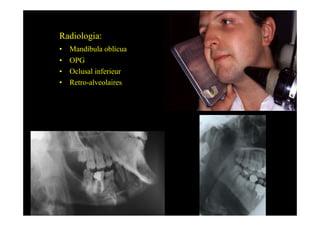

Radiologia:

•    Mandíbula oblícua

•    OPG

•    Oclusal inferieur

•    Retro-alveolaires

Oclusal                         Ralv.